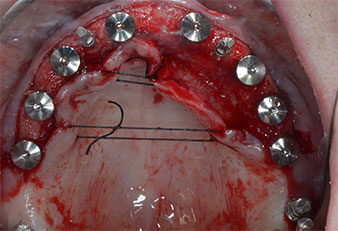

Поради сравнително твърдата кост (D2) в тази област, 10-милиметровото имплантно ложе в позиции 11 и 21 беше завършено с ротационен дрил с диаметър 4 mm в комбинация с W&H хирургичен обратен наконечник WS-75 L, W&H имплантологичен мотор Implantmed и опционалния W&H Osstell ISQ модул. За разлика от това, благодарение на меката кост, дисталните зони се подготвят до окончателен диаметър 3 mm, използвайки накрайник за Piezomed I3P. Имплантите най-накрая са поставени трансгингивално, за да остеоинтегрират за три месеца (Фиг. 6-10). Съществуващата протеза се фиксира на четирите временни импланта (Фиг. 8).

Избраната комбинирана препарационна процедура с ротационно финализиране на предните имплантни зони в твърда кост се оказва ефективна, докато пиезоелектрическата препарация е оптимална за задната мека кост с ниска остатъчна костна височина.